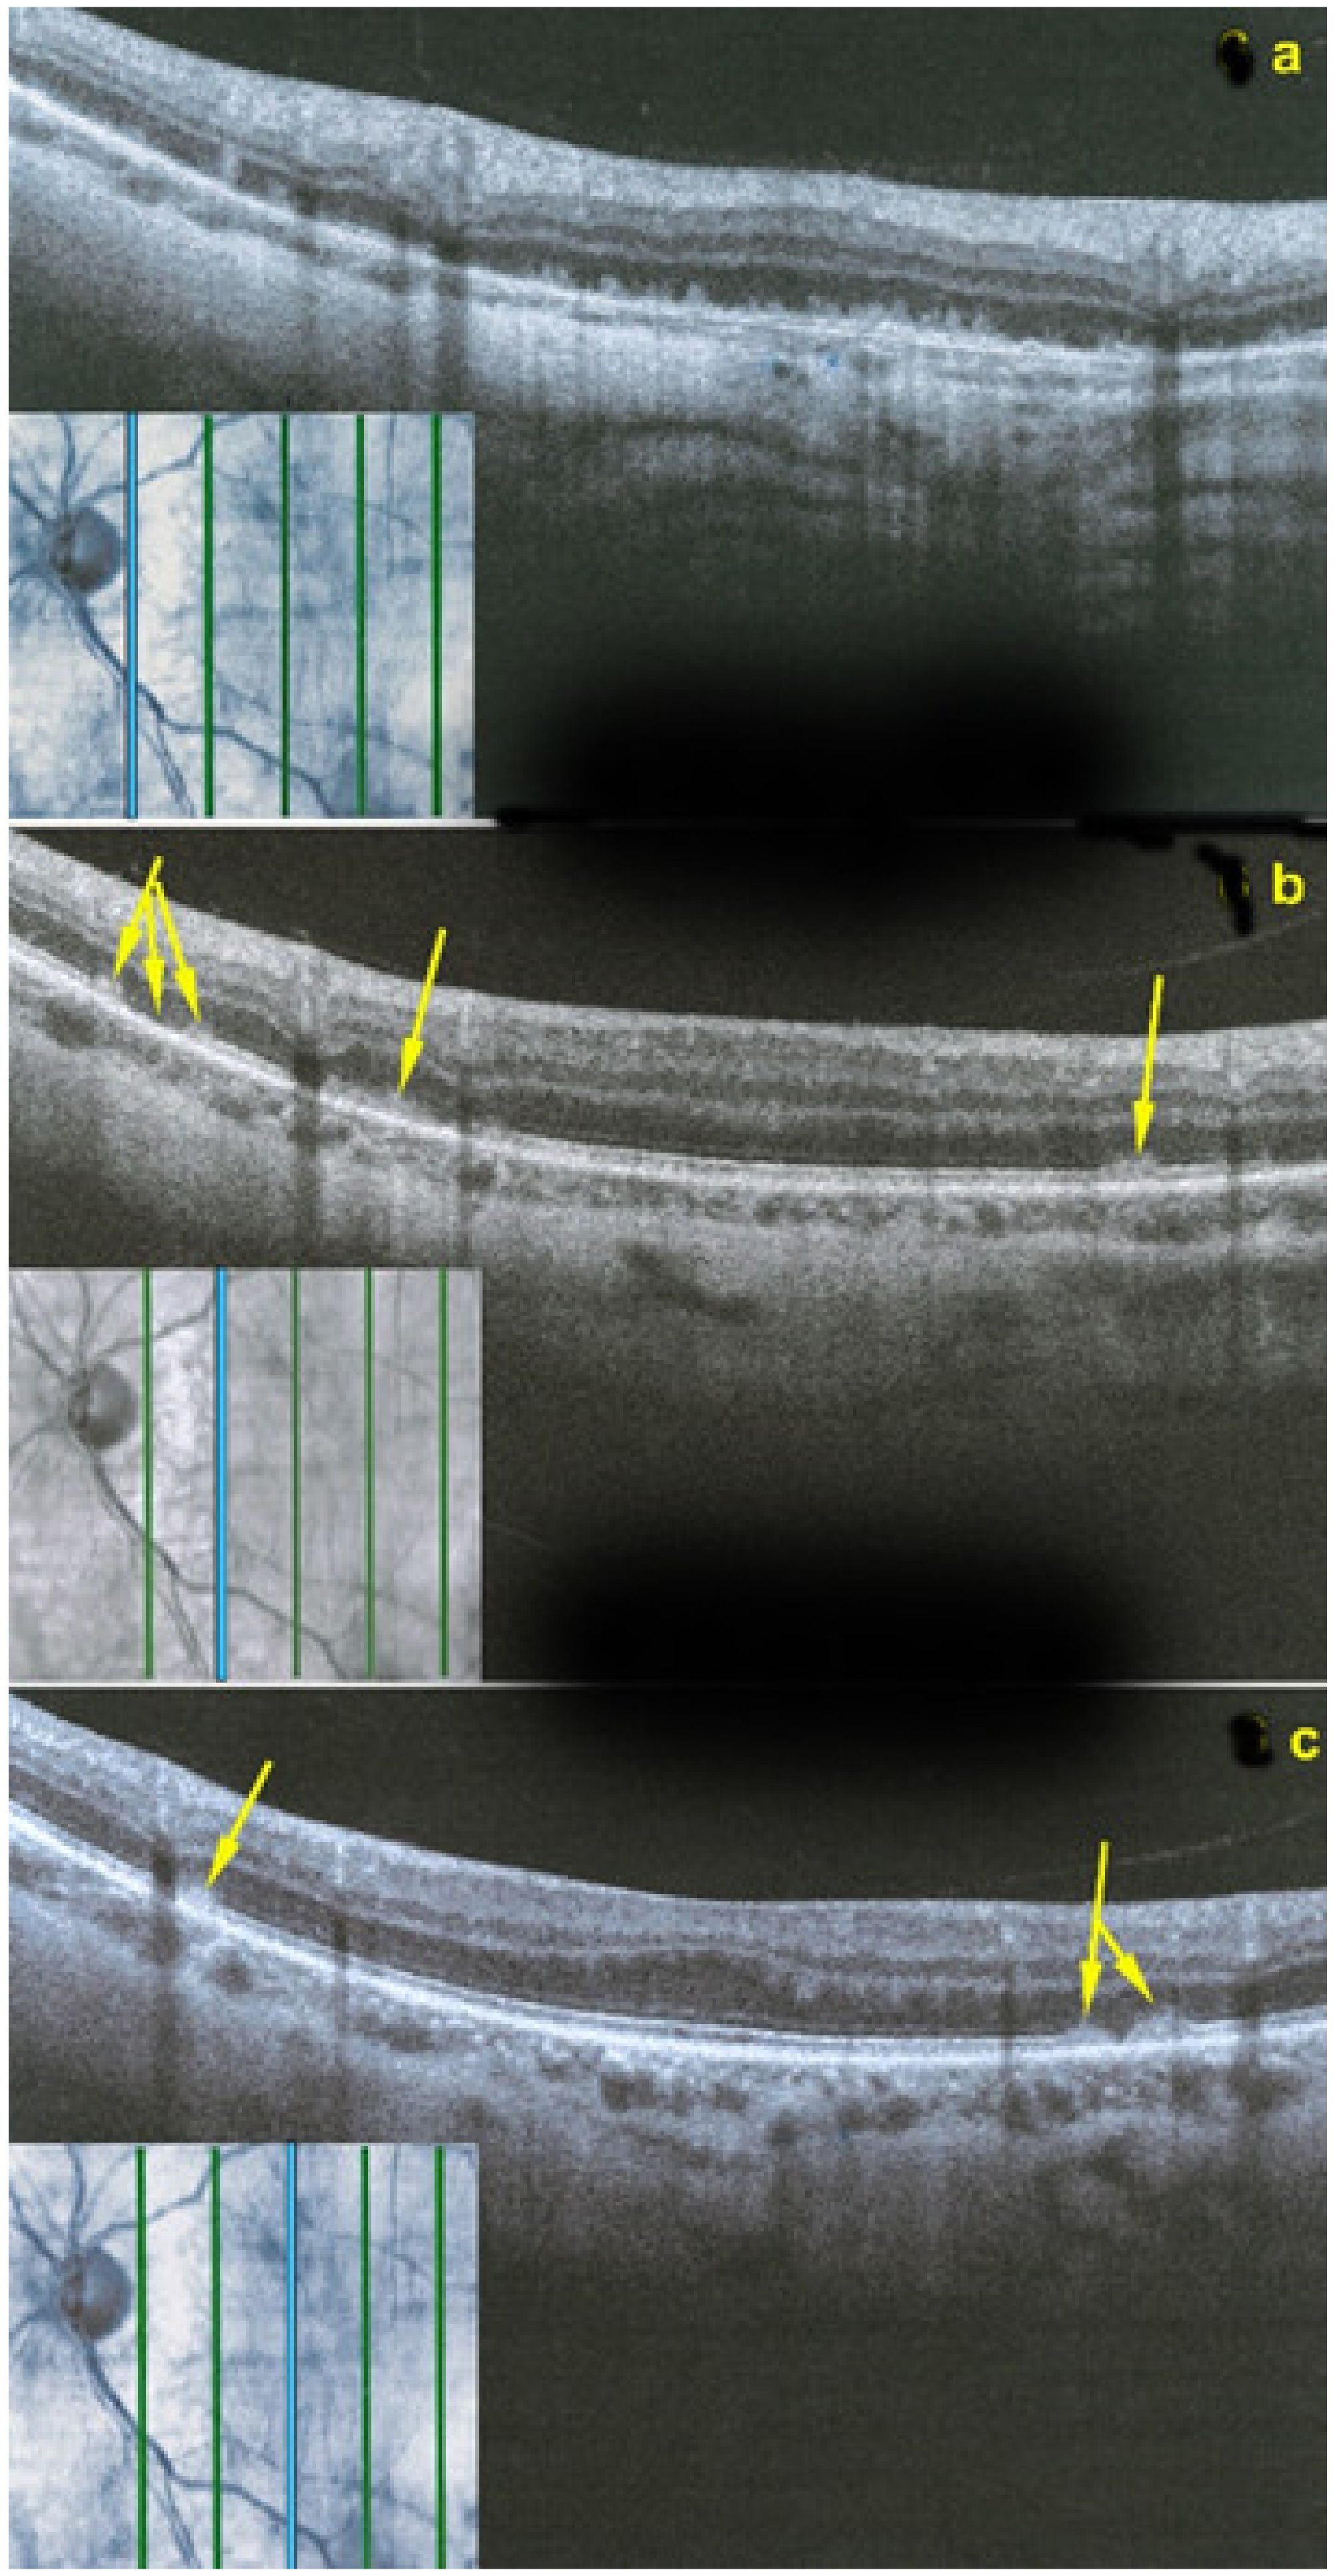

Figure 22.

OCT scans of MFC at presentation through ICGA hypofluorescent area (a), at the border of ICGA hypofluorescent area (b,c). The top set of figures (a) represents a scan going through the ICGA hypofluorescent area (FAF hyperautofluorescent) showing damaged photoreceptor outer segments with clumps throughout the whole scan. (b,c) show scans at the border of the ICGA hypofluorescent (FAF hyperautofluorescent) area with only sectorial damage to the photoreceptor outer segments (arrows) and almost normal ellipsoid zone on the most distant scan from ICGA hypofluorescent (FAF hyperautofluorescent) area.